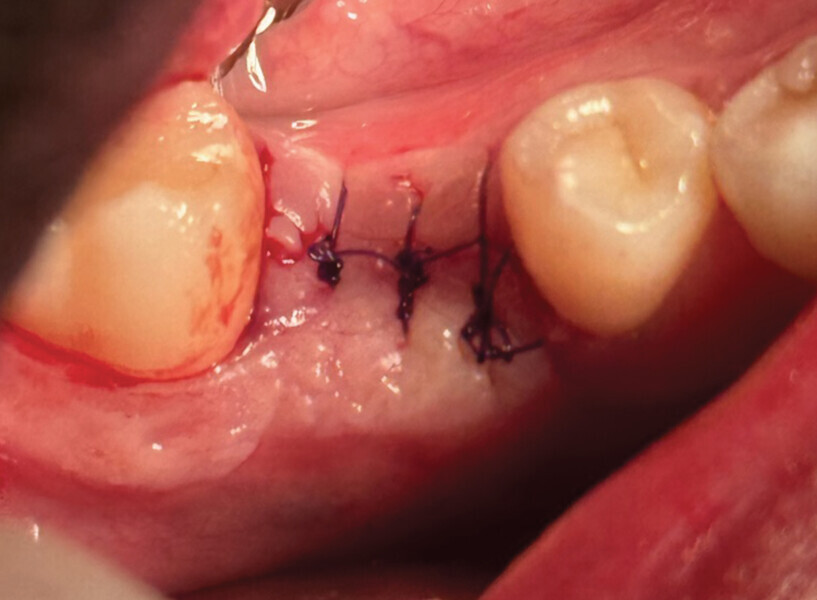

Fig. 1

Le patient, âgé de 27 ans, présentait un kyste apical ainsi qu’une atteinte de la furcation de la 46 ne nous permettant pas le retraitement et l’exérèse kystique. La décision de l’avulsion a donc été prise, en vue de la pose d’un implant (Fig. 1).

L’avulsion a été faite après anesthésie avec une ampoule de SEPANEST 40 mg adrénaline à 1/200000e. L’acte chirurgical est réalisé de manière la plus atraumatique possible, exérèse et curetage du kyste apical, nettoyage de l’alvéole. Dans ce cas précis, nous n’avons rien mis dans l’alvéole car les quatre murs alvéolaires ont pu être conservés. Un léger décollement des muqueuses vestibulaires et linguales a été nécessaire pour la mise en place de la membrane R.T.R.+.* La structure de cette membrane est faite pour être positionnée dans un sens précis, la surface lisse est toujours positionnée vers l’extérieur et la face rugueuse en regard de l’os.